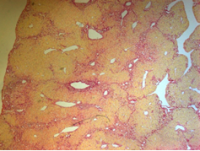

高尿酸血症模型

实验周期4周,含动物购买,随机挑选几只鼠测血清生化检测UA (血尿酸) 、BUN(尿素氮)、Scr(血肌酐)